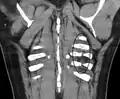

• avec les radiographies numérisées, la modification de l'exposition et du contraste permette de « fabriquer » une « fenêtre osseuse »

La société américaine de radiologie (American College of Radiology[3]) dans un document nommée Critères de pertinence, de l'ACR (ACR Appropriateness Criteria), rédigé en 1999 et révisé en 2011, indique que la radiographie de gril costal est non appropriée avec un classement d'utilité de 2/10. Ces recommandations se basent notamment sur une étude qui a démontré que la prise en charge d'un patient avec ou sans fracture costal ne différait pas[4].